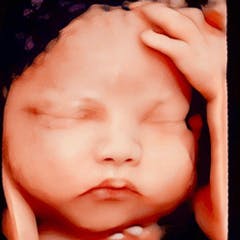

Website: https://drhoasieuam.com/thoi-diem-nao-thich-hop-de-sieu-am-4d/ Siêu âm 4D là kỹ thuật chẩn đoán hình ảnh giúp mẹ bầu quan sát trực tiếp hình ảnh và hoạt động của thai nhi trong bụng mẹ. Hình thức siêu âm này mang đến xúc cảm chân thực cho ba mẹ vì cảm giác như con đang ở ngay cạnh mình vậy✅ Siêu âm 4D còn giúp phát hiện các dị tật bẩm sinh như hội chứng Down, sứt môi, hở hàm ếch, hoặc các bất thường về tay, chân, ngón tay, ngón chân để bác sĩ kịp thời tư vấn. Website: https://drhoasieuam.com/thoi-diem-nao-thich-hop-de-sieu-am-4d/ Địa chỉ: Shop 02 chung cư Mỹ Phú, 60/68 Lâm Văn Bền, Phường Tân Kiểng, Quận 7, TP HCM. Hotline: 0907768037 Phone: 0907768037 Address: Shop 02 chung cư Mỹ Phú, 60/68 Lâm Văn Bền, Phường Tân Kiểng, Quận 7, TP HCM